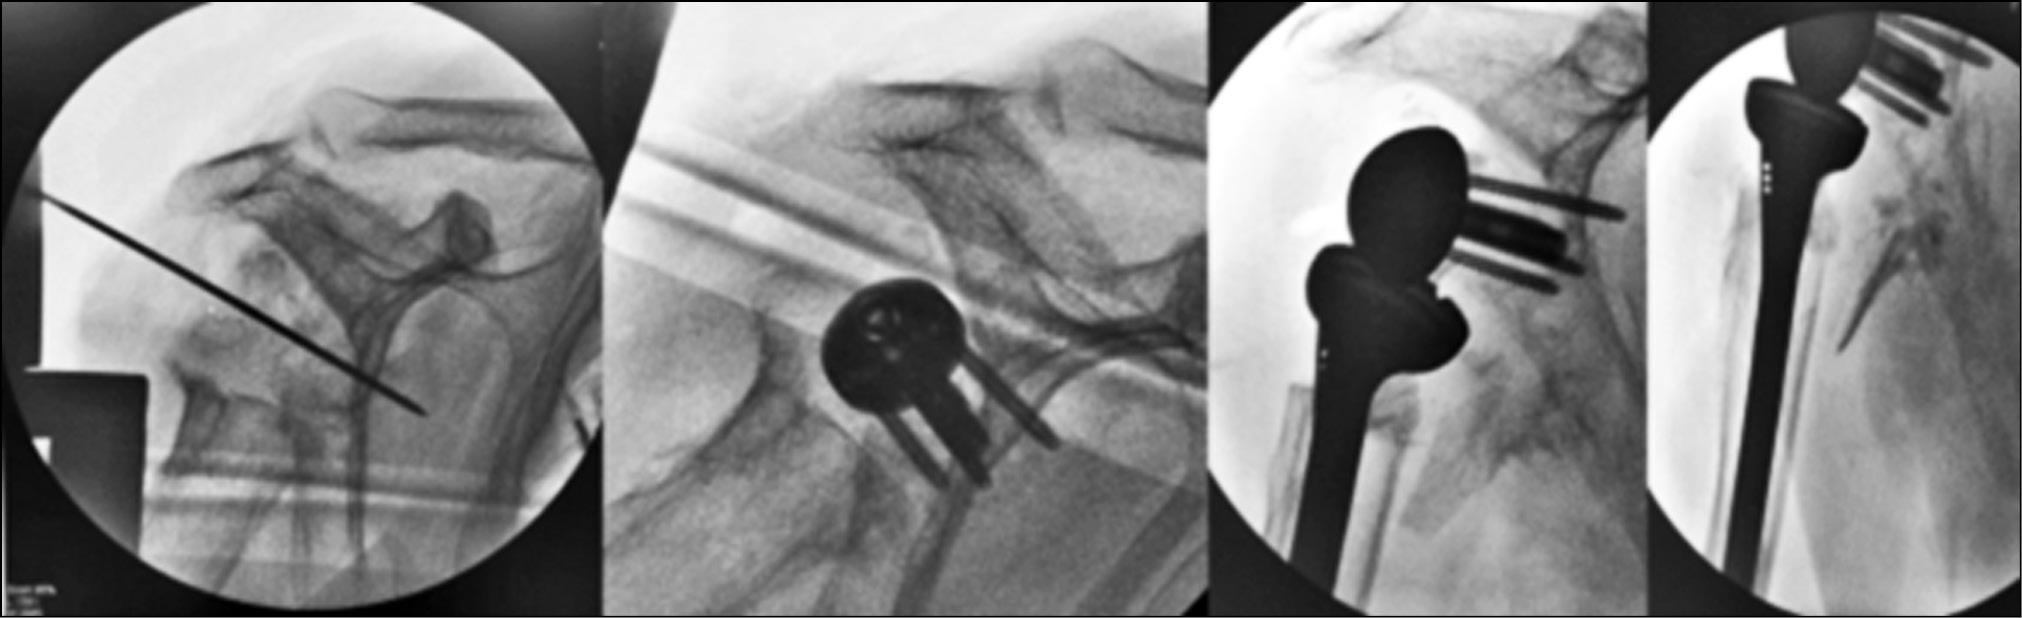

Reverse shoulder arthroplasty was performed with replacement of a significant bone defect in the glenoid using a graft from the iliac crest, according to the method described above (Figs. 5 and 6).

Fig. 6. Needle graft implantation, metaglene insertion

All stages of surgery must take place under the control of an electro-optical converter (Fig. 7). Postoperatively, an external immobilization of the operated limb with an orthosis, removable for rehabilitation measures, was performed. The patient followed a rehabilitation course, which included mechanotherapy and electrical stimulation of the deltoid muscle in the early stages after surgery.

Fig. 7. Step-by-step intraoperative X-ray control